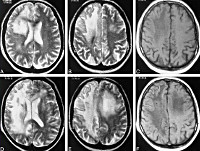

• МРТ головного мозга. Обнаруживается диффузная мультифокальная демиелинизация, очаги имеют различный размер, асимметрично располагаются в белом веществе, таламусе, базальных ядрах.